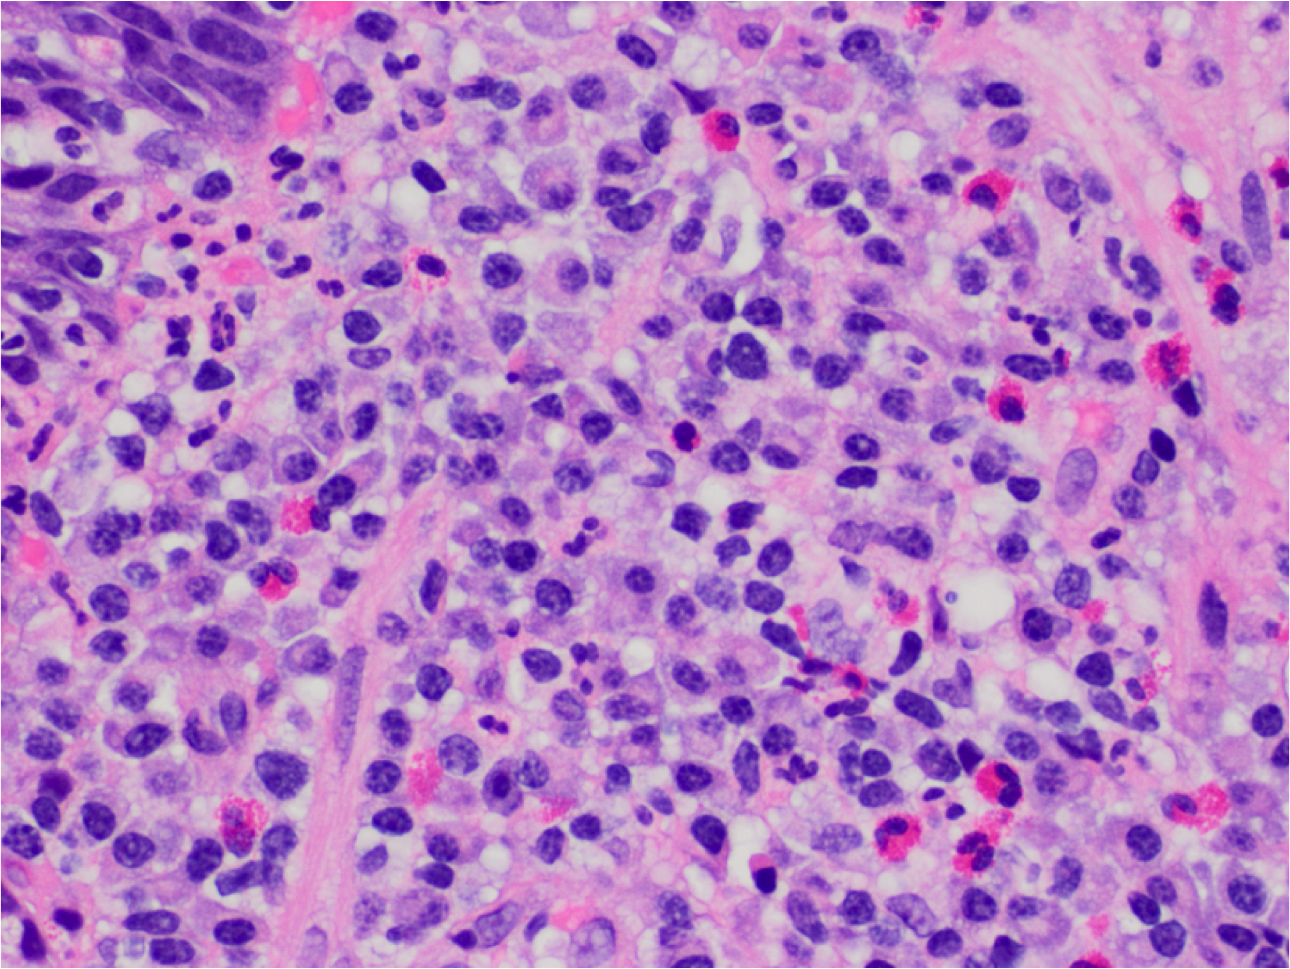

What’s this? notable features?

Barrett’s Esop with high-grade dysplasia and adenocarcinoma.

Intestinalised mucosa with villous architecture, nuclear enlargement and no maturation.